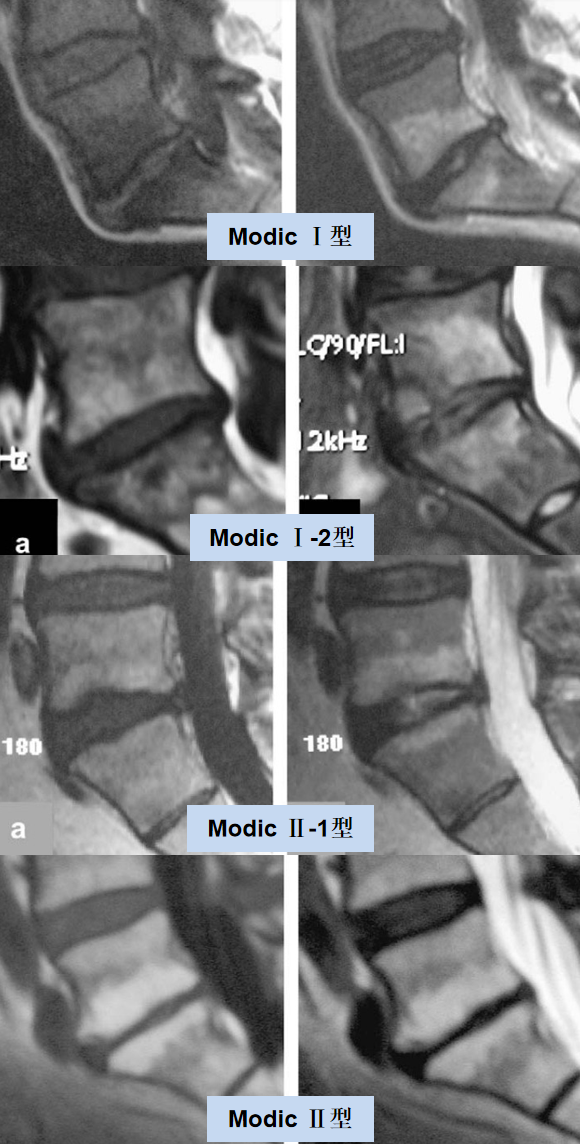

2009 年,Fayad 等在经典分型基础上,提出混合型的分型:

Modic I-2 型:混合性水肿和脂肪改变,以水肿为主;

Modic II-1 型:混合性水肿和脂肪改变以脂肪变性为主。

Modic影像表现:

Ⅰ型:组织学表现为终板及终板下区域有丰富的肉芽组织长入, 纤维血管组织代替了增厚的骨小梁间的正常骨髓,从而延长了椎体 T1、T2 驰豫时间,T1WI 上终板及邻近骨质表现为低信号,T2WI 上表现为高信号,抑脂序列呈高信号,表明骨髓水肿。

Ⅱ型:组织学表现为骨髓脂肪变性或骨髓缺血坏死,导致 T1 及 T2 时间缩短,在 T1WI 上呈高信号,T2WI 表现为稍高信号,抑脂序列呈低信号;